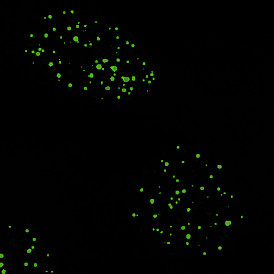

The IF Dots App provides dot detection per cell within the cell compartments for up to four markers in a sample (e.g., FISH, RNA, oil droplets). Each segmented cell compartment is measured for up to 20 intensity, statistic, and morphometric parameters. Dot measurement parameters are provided per cell compartment (e.g., nucleus, cytoplasm) and per dot and include count, mean intensity, total dot area, the sum of intensity.

App Category 2